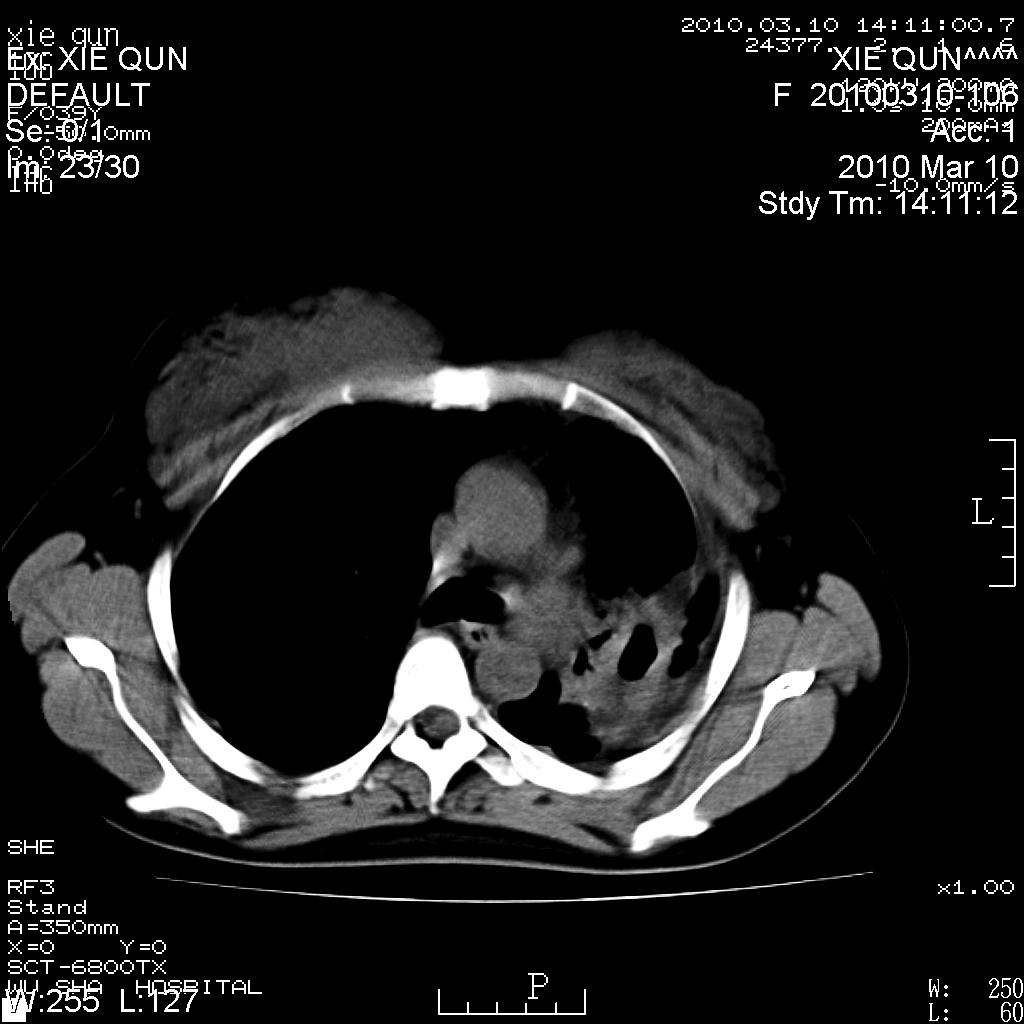

以下是引用心路寻觅在2010-3-24 17:28:00的发言:[br]两肺继发性tb左上肺空洞形成,建议痰检明确诊断。

以下是引用随光逐影在2010-3-24 19:19:00的发言:[br]两肺继发性结核并左上肺上叶空洞形成。